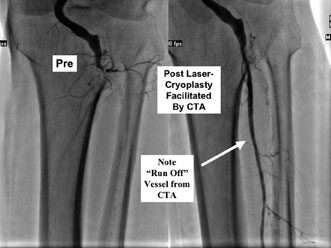

Most patients with diabetes who do suffer from severe infrapopliteal CTOs have the phenomenon of “pedal sparring.” This refers to the fact that the dorsalis pedis artery (DPA) and/or posterior tibial artery (PTA) below the level of the ankle will often be free of obliterative disease. These arteries are patent and be perfused by a collateral artery network, revealing a “distal vascular target” appropriate for revascularization. This presents an opportunity for either surgical or endovascular revascularization.

This becomes very important with committed limb salvage angiography and during CTA. If physicians are not aware of this “pedal sparring,” they will not consider revascularization and their imaging will be inadequate. Patients often receive referrals for primary amputation when they actually have the potential for revascularization.